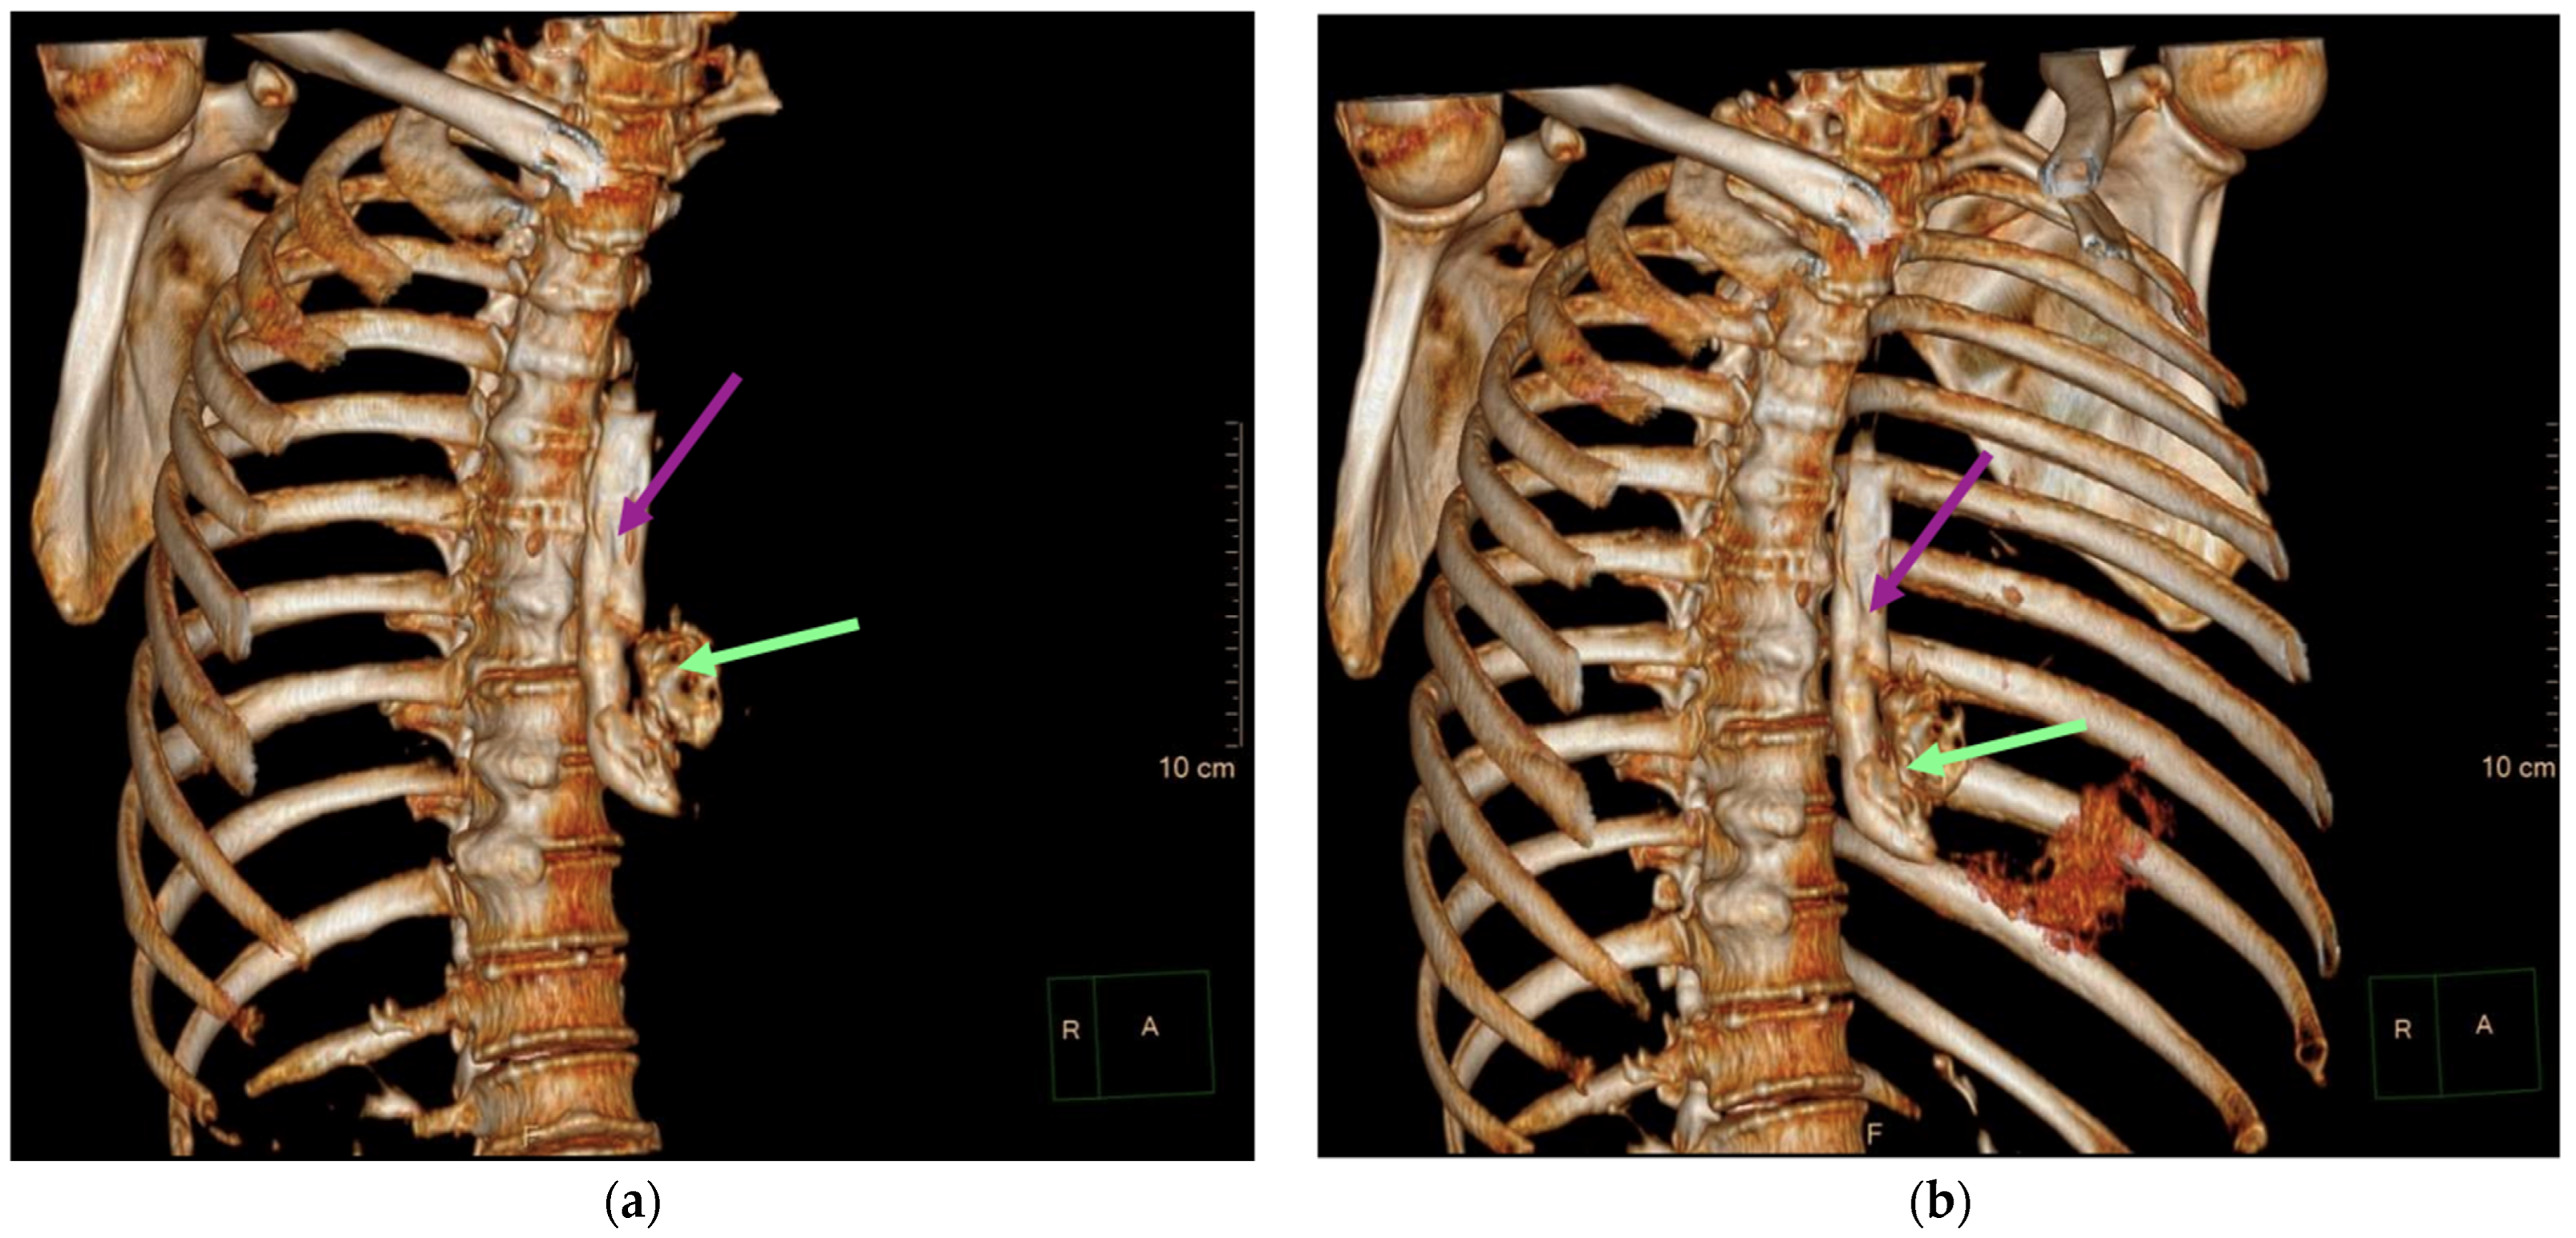

2. Case